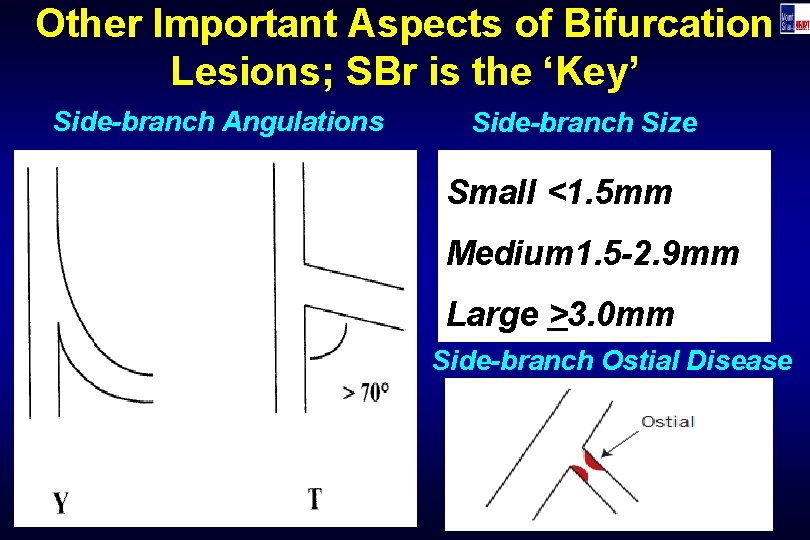

Other Important Aspects of Bifurcation Lesions; SBr is the ‘Key’ Side-branch Angulations Side-branch Size Small <1. 5 mm Medium 1. 5 -2. 9 mm Large >3. 0 mm Side-branch Ostial Disease